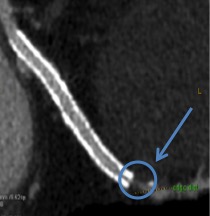

TC CORONARICA (FASE ANATOMICA A RIPOSO)

L’immagine di sinistra mostra una stenosi anatomicamente severa al tratto medio dell’arteria discendente anteriore. L’immagine di destra mostra pervietà degli stent su arteria circonflessa-ramo marginale ma presenza di stenosi critica sul vaso nativo a valle dello stent.